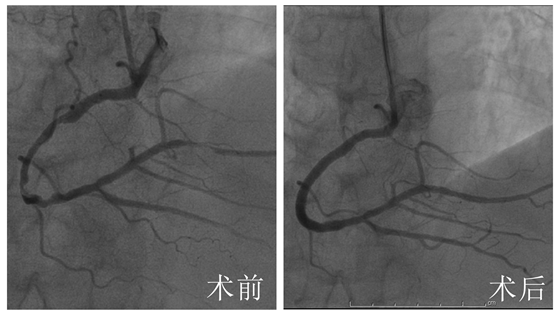

3月22日,彭道地主任及范爱德副主任医师同台完善冠脉造影+支架植入术示:冠脉血管多支多处严重狭窄,右冠弥漫性狭窄次全性闭塞,并在右冠病变处植入支架3枚,狭窄病变血管开通,症状也就随之消失了。